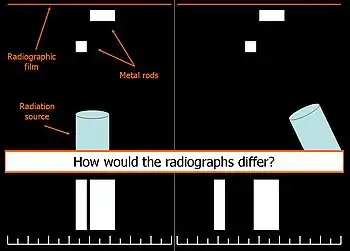

In 1909, Charles A. Clark described a radiographic procedure for localizing impacted teeth to determining their relative antero-posterior position.[1] If the two teeth (or, by extension, any two objects, such as a tooth and a foreign object) are located in front of one another relative to the x-ray beam, they will appear superimposed on one another on a dental radiograph, but it will be impossible to know which one is in front of the other. To determine which is in front and which is behind, Clark proposed his SLOB rule, as a complicated set of three radiographs, but which can be simplified as follows using just two:

- Expose another film while angle of the x-ray beam has been changed. If an object moves in the same direction as the source of the x-ray beam, it is lingual to the other object. If the object moves in the opposite direction of the source, it is buccal to the other object.

In 1952, Richards amended this rule using only 2 radiographs,[2][3] asserting that the object positioned more buccally will move more relative to the object positioned more palatally or lingually.

As a generalization, but not specifically stated as part of Richards' buccal object rule, the more buccal an object is (i.e. the closer it is to the x-ray source) the more it will move in the second radiograph when repositioning the x-ray source.